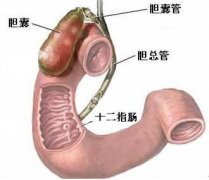

十二指肠炎的早期症状有哪些?会引发哪些危害

导语 导致十二指肠炎的情况有好多种,主要原因是幽门螺杆菌感染、胃酸过多

十二指肠溃疡有哪些症状,什么病因引起的

导语 十二指肠溃疡是消化科常见病之一,十二指肠任何部位都可发生溃疡,但

如何治疗十二指肠溃疡

导读 十二指肠溃疡是消化科常见病之一,十二指肠任何部位都可发生溃疡,但

十二直肠溃疡的症状

导读 十二指肠溃疡是消化科常见病之一,十二指肠任何部位都可发生溃疡,但 查看更多